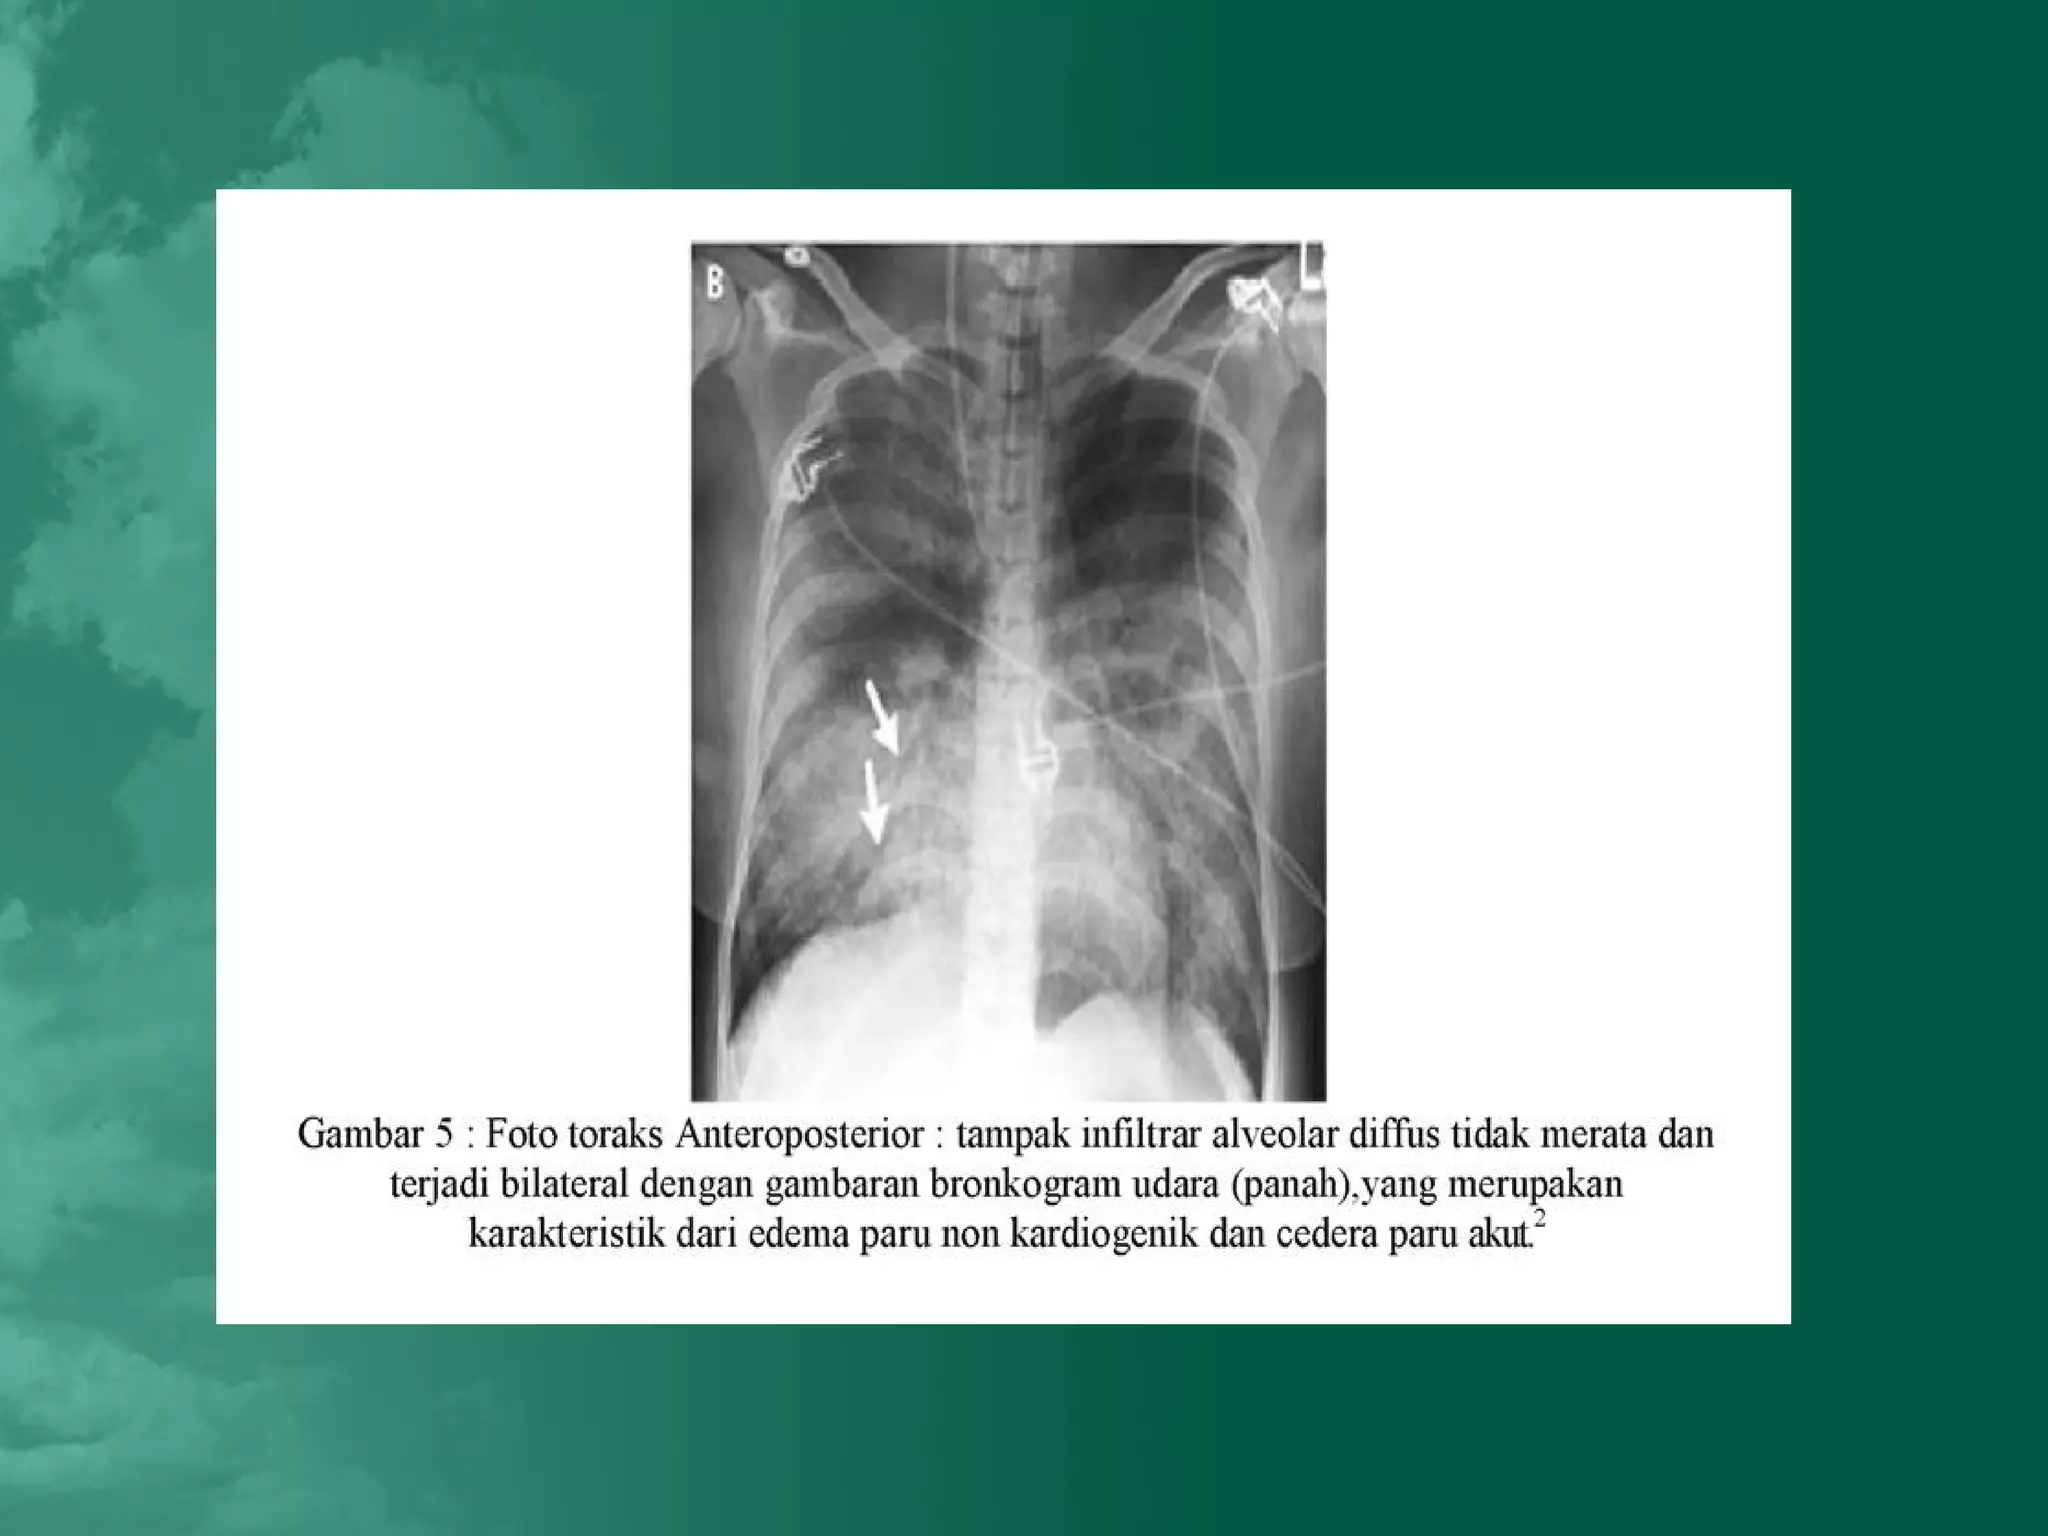

Foto toraks

PEMERIKSAAN PENUNJANG Darah rutin,Kultur darah Analisa gas darah Foto toraks Analisa cairan edem Pulmonary – Artery Catheterization